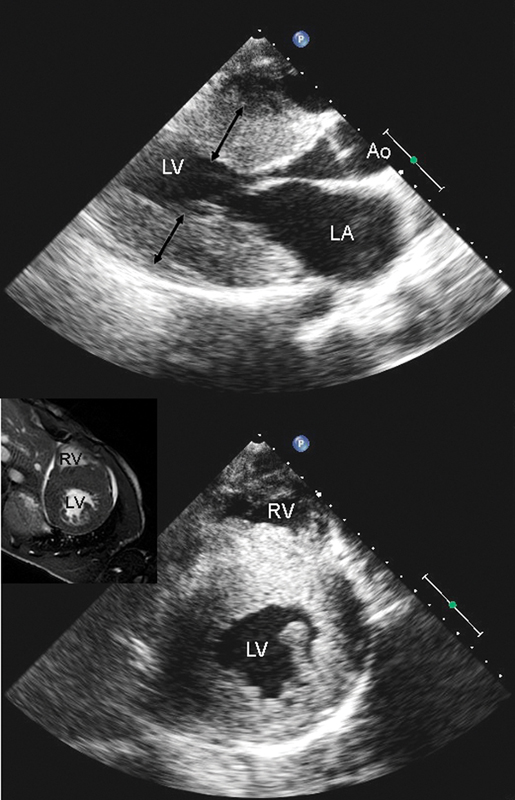

فحوصات تشخيصية لبعض امراض القلب والشرايين التاجية